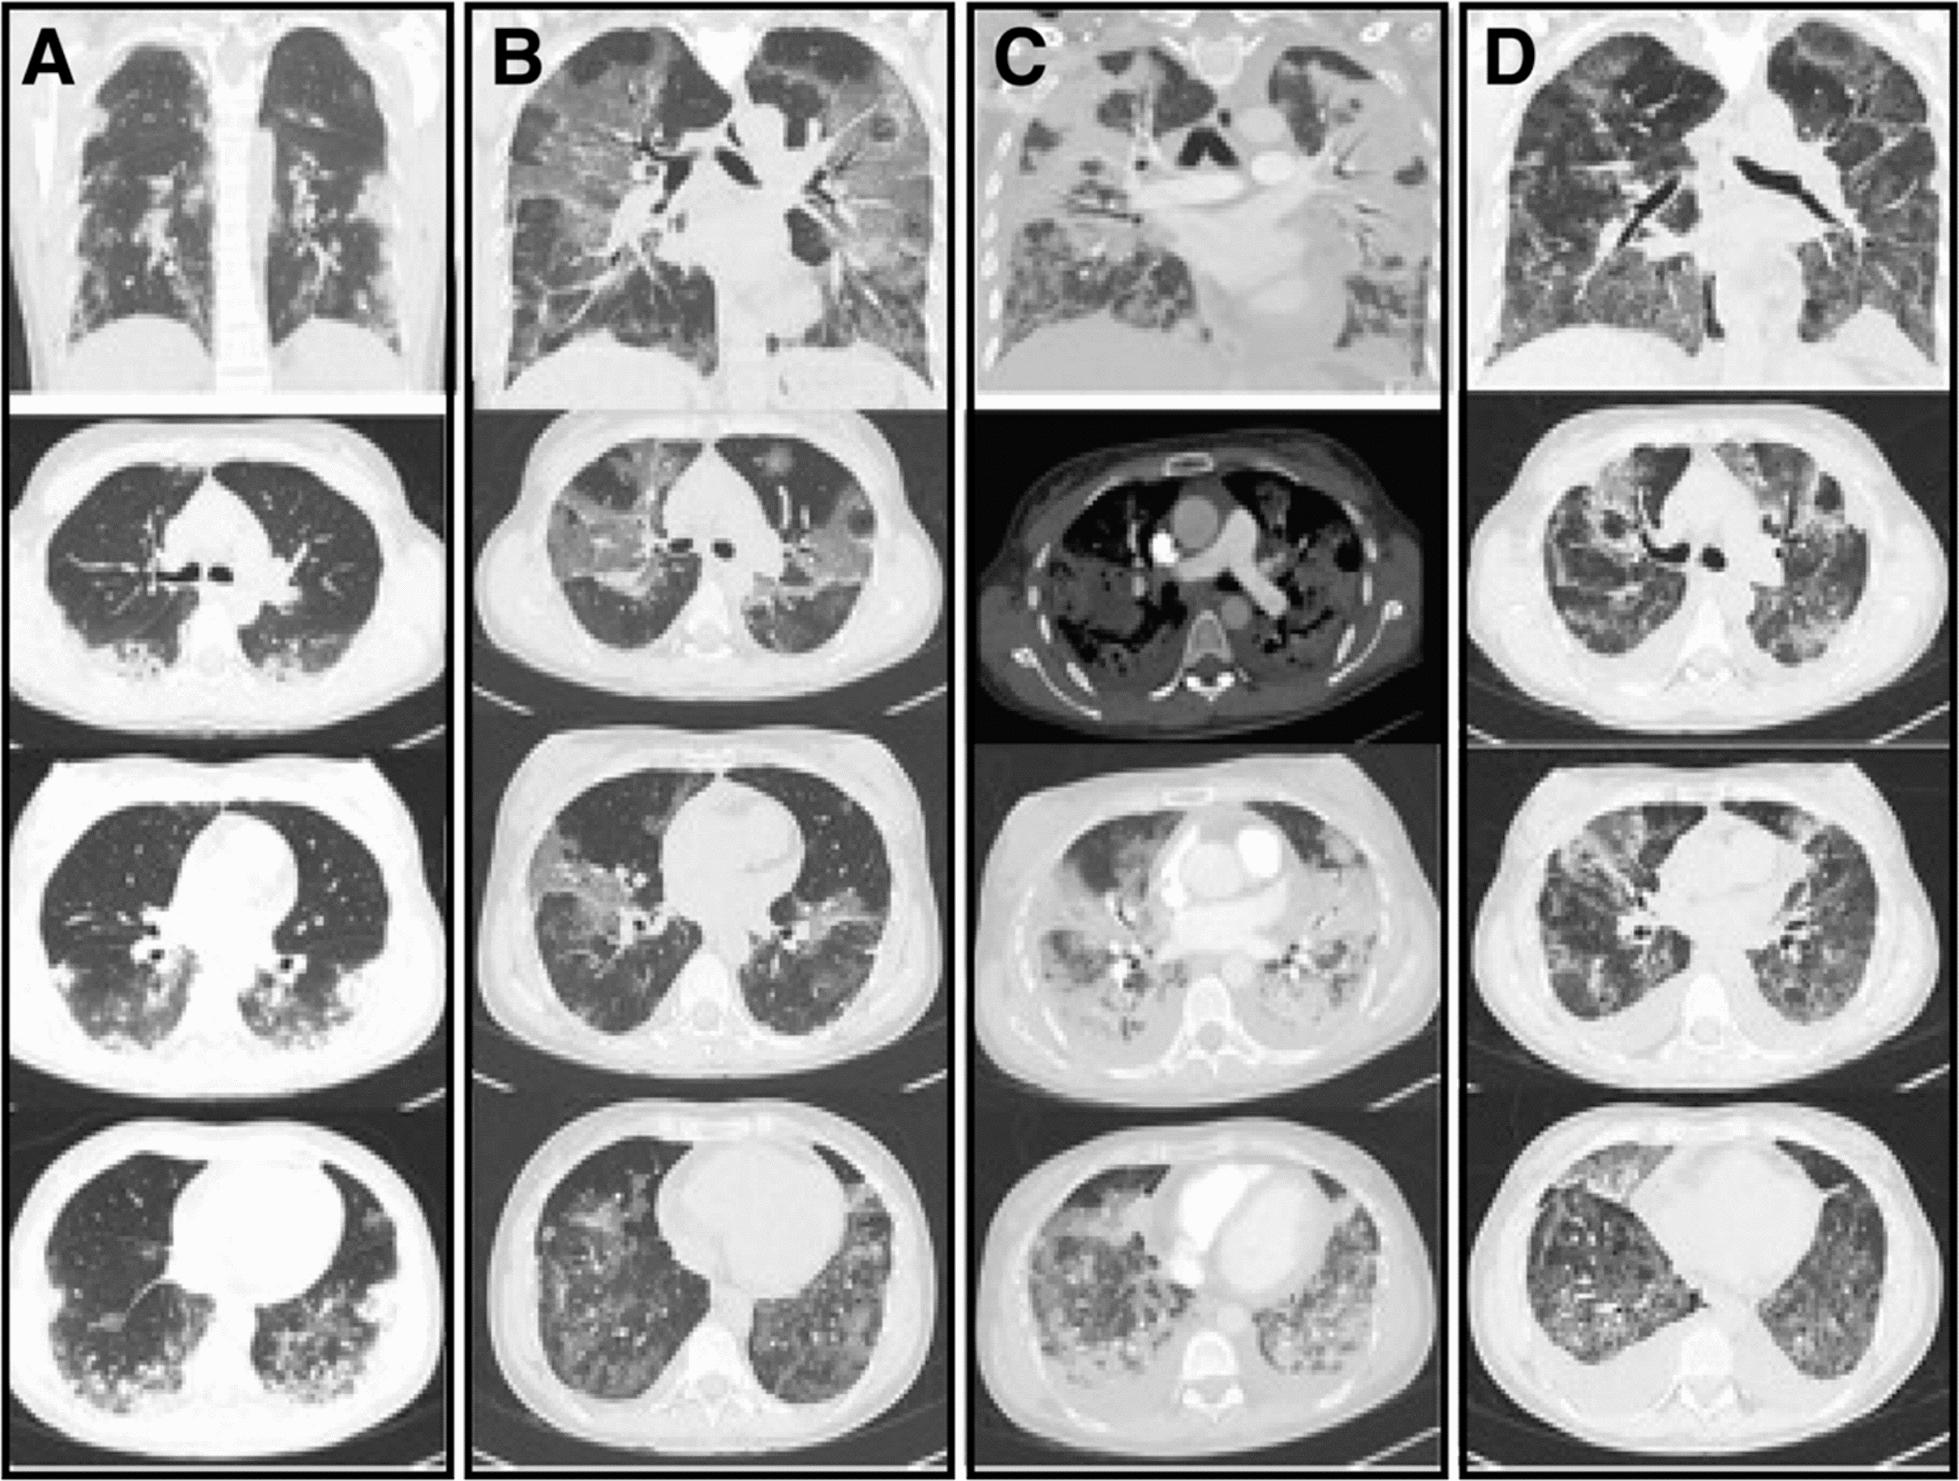

We report three cases involving mixed-race Colombian female patients aged 58, 35, and 63 years who experienced multiple episodes of coronavirus disease 2019 infection, with the most recent episode progressing to critical illness. These cases were characterized by relapses or persistent infections, and genomic analyses consistently identified the Omicron severe acute respiratory syndrome coronavirus 2 lineage as the causative variant. Notably, individuals with underlying immunosuppressive conditions developed severe acute respiratory syndrome coronavirus 2 infections that were more severe, leading to fatal outcomes that included acute respiratory distress syndrome, multiorgan dysfunction, and death. In contrast, one vaccinated patient with significant comorbidities exhibited persistent critical coronavirus disease 2019 but responded positively to treatment with tocilizumab.

我们报告了三例涉及不同种族的哥伦比亚女性患者的病例,年龄分别为58岁、35岁和63岁,她们经历了多次2019年冠状病毒病感染,最近一次感染进展为危重症。这些病例的特征是复发或持续感染,基因组分析一致确定奥密克戎严重急性呼吸综合征冠状病毒2谱系为致病变体。值得注意的是,患有潜在免疫抑制疾病的个体发生的严重急性呼吸综合征冠状病毒2感染更为严重,导致包括急性呼吸窘迫综合征、多器官功能障碍和死亡在内的致命后果。相比之下,一名患有严重合并症的接种疫苗患者表现出持续的2019年冠状病毒病危重症,但对托珠单抗治疗反应良好。